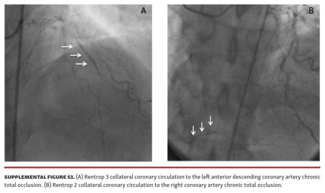

This study evaluates the relationship between endothelial progenitor cell count and function and collateral circulation in coronary chronic total occlusions.

Mustafa Ebik, MD; Cihan Ozturk, MD

A 50-year-old man was admitted to the emergency room with unstable angina pectoris.

A 75-year-old woman with hypertension, hypothyroidism, and diabetes was referred to the cath lab due to non-ST segment elevation myocardial infarction.